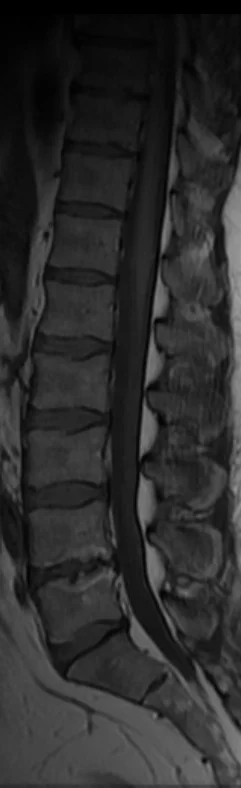

Mä pistän tohon pari croppausta noista magneettikuvista, jos ette oo nähny miltä "diskusdegeneraatio" näyttää. Ja vielä voimakasasteinen sellainen. Ei tarvi olla tosiaan radiologian erikoislääkäri nähdäkseen noista että vikaa on kun vertaa tota yhtä kohtaa muihin välilevyihin.

• MRIKoko.webp

MRIKoko.webp

10,7 KB · Katsottu: 828